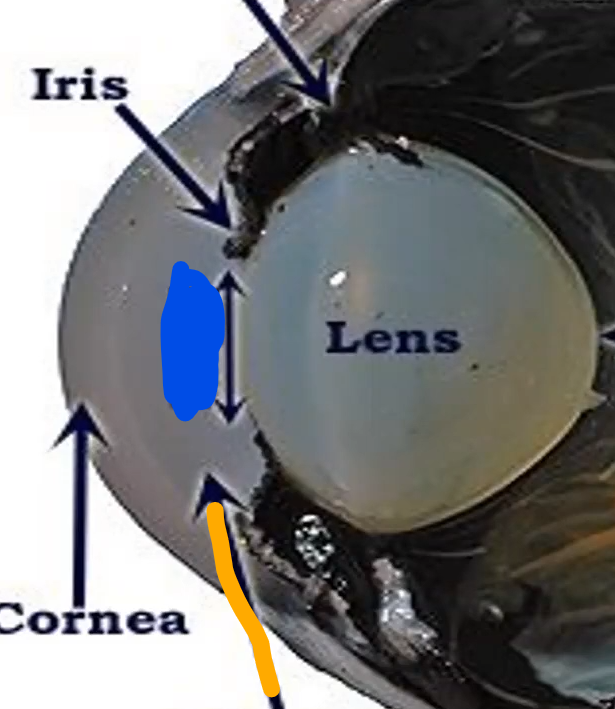

Orange

Iris

Blue

Pupil/lens

Red

Lens

Blue

Retina

Gray

Iris

Blue

Pupil